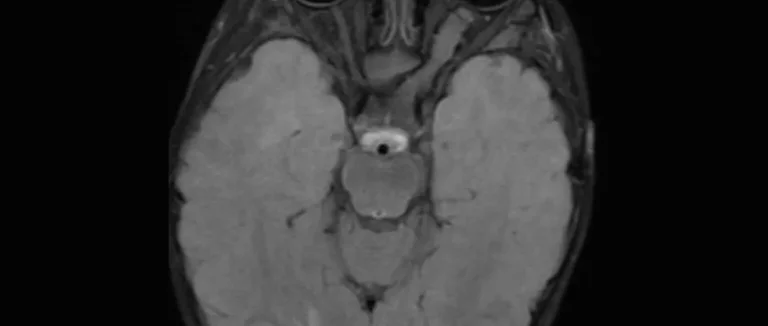

cerveau

glioblastome

glioblastome multiforme

Méningiomes